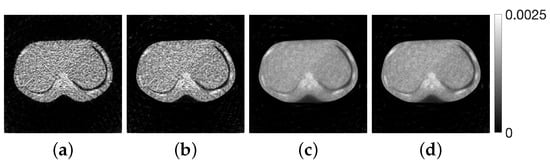

4.2. Experimental Results

| Method | Dist. Func. | SSIM | Std. Dev. | ||

|---|---|---|---|---|---|

| MLEM | — | 1 | 1 | 0.816 | 0.111 |

| (a) | 1.219 | 0.744 | 0.813 | 0.122 | |

| (b) | 0.957 | 1.39 | 0.798 | 0.118 | |

| PDEM | (c) | 0.139 | 9.21 | 0.983 | 0.0719 |

| (d) | 0.143 | 9.17 | 0.982 | 0.0727 | |

| (e) | 0.166 | 3.45 | 0.981 | 0.0517 |